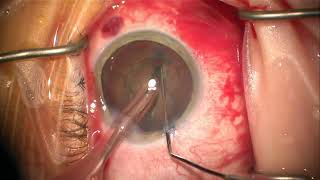

Resident Cataract Surgery (case #32)

Resident Cataract Surgery (case #32) resident cataract surgery final exam!

Resident Cataract Surgery (case #32)

Resident Cataract Surgery (case #32) resident cataract surgery final exam!